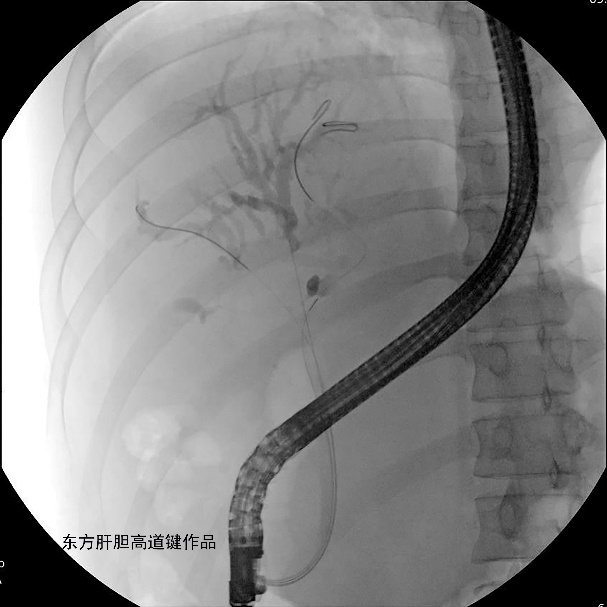

图F:再释放左内侧肝内胆管的金属支架,保留3根导丝在位,在原先留置于左外侧肝内胆管导丝的指引下,第四根导丝顺利从左内侧肝内胆管金属支架网眼穿过进入左外侧肝内胆管,但反复尝试,6F扩张导管无法通过金属网眼;

图G:沿第三根位于左外侧肝内胆管导丝插入6F扩张导管顺利通过狭窄段进入左外侧肝内胆管;

图H:沿第三根导丝置入第三根金属支架并顺利释放;

图L:三根金属支架定位良好。